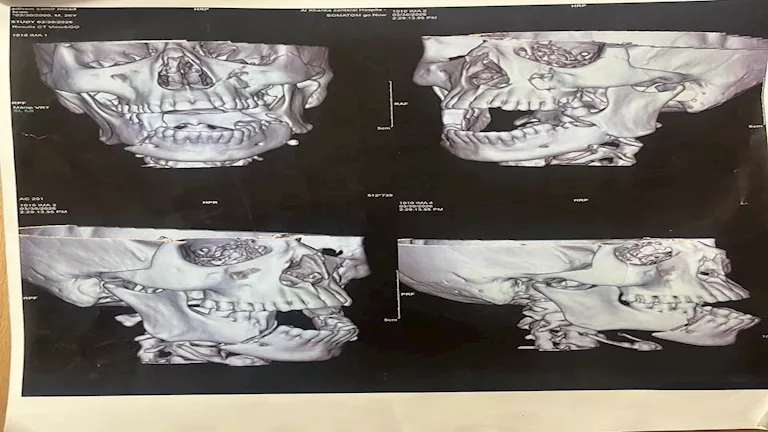

أوضح بيان المستشفى أن الحالة الأولى لشاب يبلغ من العمر 26 عامًا، وصل إلى قسم الطوارئ مصابًا بكسر مضاعف في الفك السفلي نتيجة حادث طريق، حيث تم التدخل الجراحي العاجل لتثبيت الكسور باستخدام شرائح معدنية، إلى جانب إجراء خياطة تجميلية دقيقة ساهمت في استعادة وظائف الفك والحفاظ على الشكل الجمالي.

أما الحالة الثانية، فكانت لمريض يبلغ من العمر 40 عامًا، تعرض لإصابات بالغة شملت كسورًا في عظمة الوجنة ومحجر العين، حيث تم التعامل معها من خلال تدخل جراحي دقيق لتثبيت الكسور وإعادة ترميم محجر العين، مع متابعة طبية مكثفة لضمان سلامة النظر والوظائف الحسية، حتى استقرت حالته.